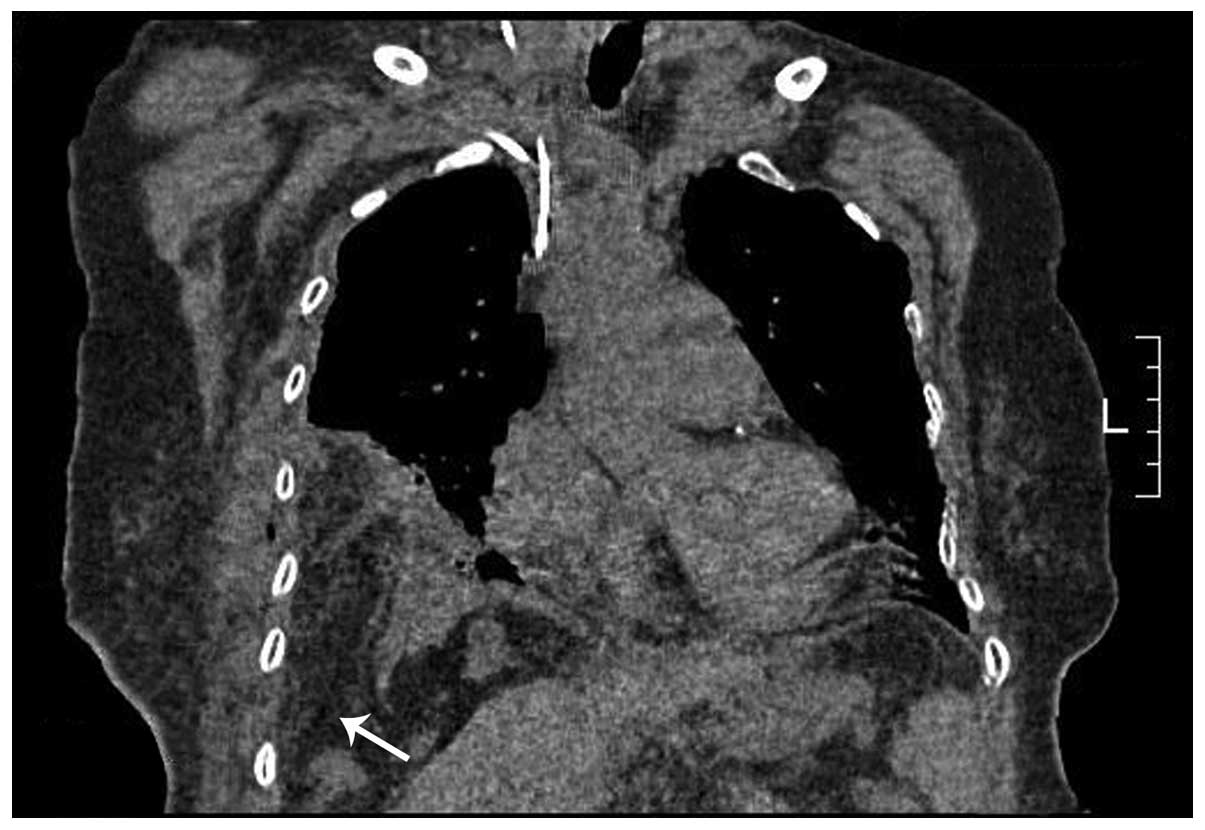

Diaphragmatic perforation with colonic herniation due to hepatic radiofrequency ablation: A case report and review of the literature

Radiofrequency ablation (RFA) has been widely accepted as an alternative treatment for unresectable primary and metastatic hepatic tumors, with satisfactory rates of local response and significant improvements in rates of overall survival. Numerous large series studies have shown that RFA is safe and effective, with a low mortality rate and a low major complication rate. Major complications, including diaphragmatic perforation and hernia, have rarely been previously reported. The current case report presents a case of diaphragmatic hernia with perforation of the incarcerated colon in the thoracic cavity 12 months following hepatic RFA, and reviews nine previously reported cases of diaphragmatic hernia. Comprehensive analysis of the nine cases demonstrated possibilities leading to diaphragmatic hernia following diaphragmatic thermal injury as a consequence of hepatic RFA. Clinicians and radiologists must consider diaphragmatic thermal damage following hepatic RFA for liver tumors adjacent to the diaphragm, particularly for patients with symptoms of ileus, dyspnea, chest pain, pleural effusion and right shoulder pain.

Figure 2